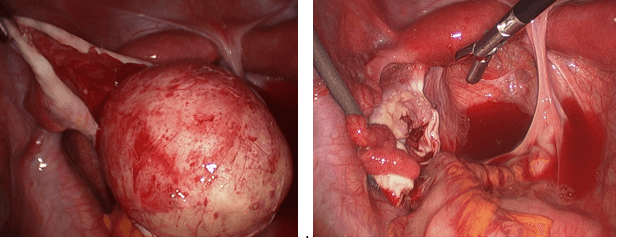

The photos below show several different types of ovarian masses:

Left photo – a greatly enlarge right ovary containing a dermoid cyst. Right photo – after the dermoid had been removed by laparoscopy.